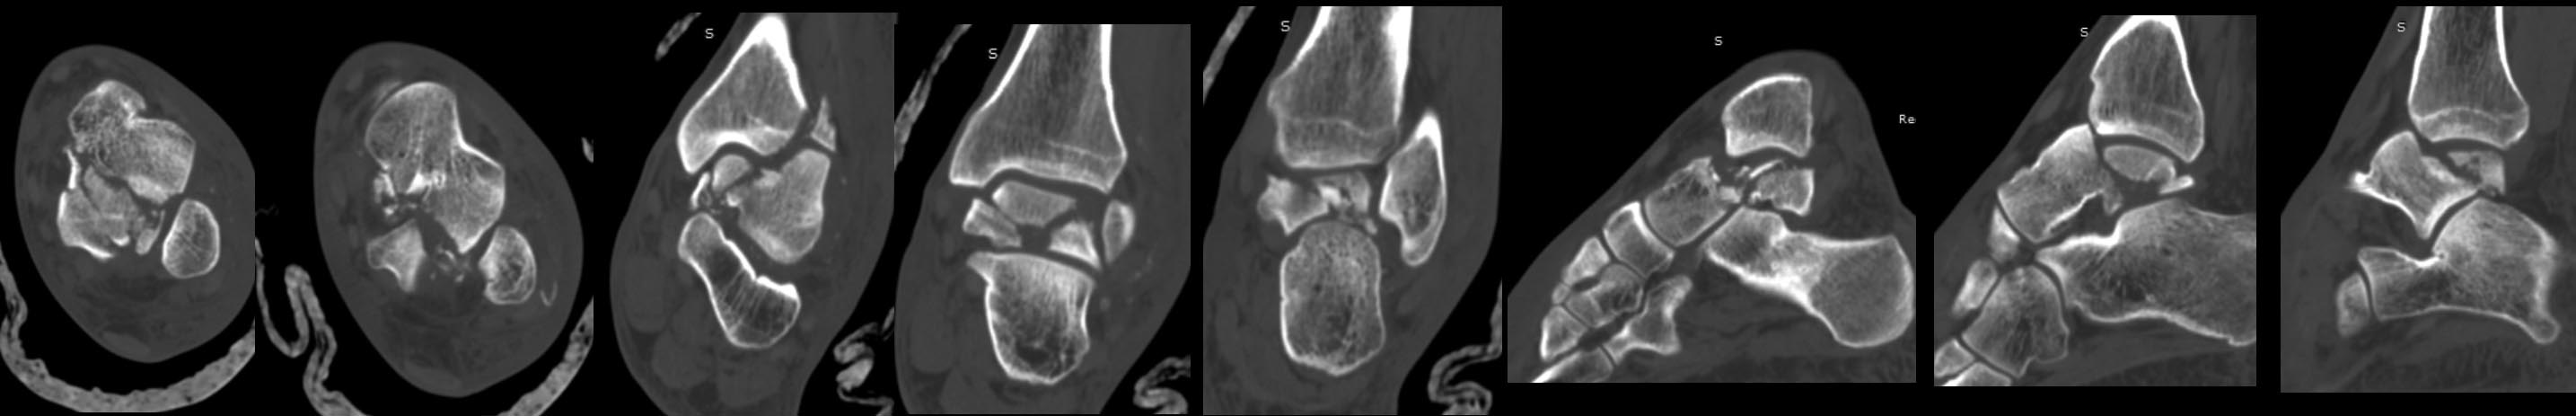

Перелом тела таранной кости.Первичнй артродез .

Дублирую фото рентгенограммы и СКТ

Имя     : ct.jpg

Тип     : image/jpeg

Размер  : 103124 байтов